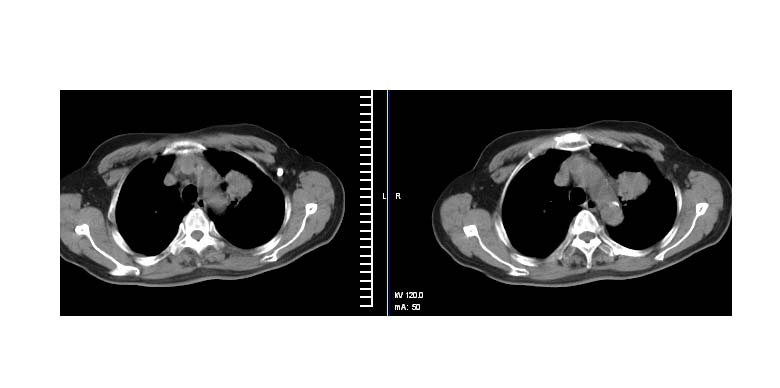

左上肺周围型肺癌伴纵隔淋巴结转移

左上肺实质性肿块,浅分叶 毛糙 胸膜凹陷征 纵隔淋巴结肿大——支持:左肺上叶周围型肺癌!

考虑左上肺周围型肺癌伴纵隔淋巴结转移。

左上肺软组织肿块,有分叶,短毛刺,气管旁间隙见有肿大淋巴结,考虑左上周围型肺癌伴纵隔淋巴结转移。

左上肺周围型肺癌伴纵隔淋巴结转移。

考虑左上肺周围型肺癌伴纵隔淋巴结转移

左上肺癌并纵隔淋巴结转移!